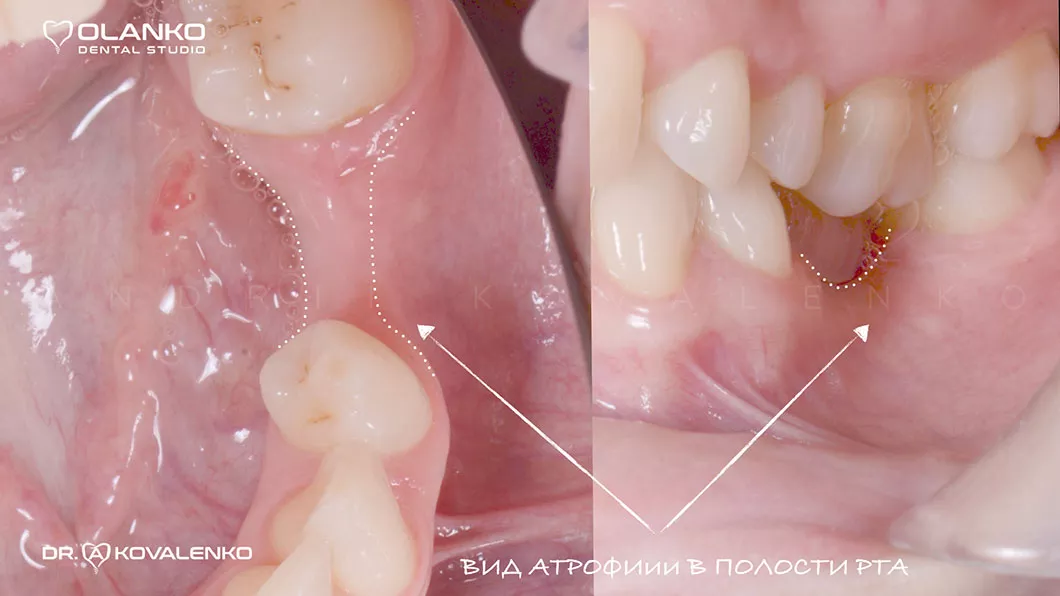

Атрофія - це прогресуюче зменшення кісткової тканини, що супроводжується також і зменшенням ширини та висоти альвеолярного гребеня. Розвивається після видалення зуба і є найпоширенішою перешкодою для встановлення зубного імплантату.

Атрофія - це прогресуюче зменшення кісткової тканини Оланко Броврари Київ

Спеціалісти Olanko dental studio (Оланко) м. Бровари рекомендують проводити операцію по встановленню зубного імплантату в максимально ранній період після видалення проблемного зуба (від 3 до 6 місяців), або використовувати методику імплантації одномоментно з видаленням зуба лише тоді, коли є умови для проведення такої операції. Але якщо зменшення кісткової тканини вже є, ми вдаємося до використання хірургічного відновлення обсягів кісткової тканини - кісткової пластики.